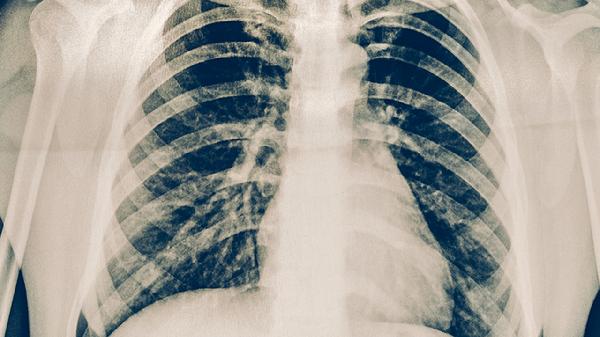

肺结核的临床表现主要有咳嗽、咳痰、咯血、胸痛、发热等。肺结核是由结核分枝杆菌感染引起的慢性传染病,主要通过呼吸道传播,患者需及时就医并接受规范治疗。

肺结核患者早期常出现持续性干咳,随着病情进展可转为咳痰。咳嗽多发生在清晨或夜间,持续时间较长。结核分枝杆菌感染导致肺部组织发生炎症反应,刺激支气管黏膜引起咳嗽反射。患者可遵医嘱使用异烟肼片、利福平胶囊、吡嗪酰胺片等抗结核药物进行治疗。

肺结核患者咳出的痰液多为白色黏液痰,病情加重时可出现黄绿色脓性痰。当肺部病灶与支气管相通时,痰中可能带有干酪样坏死物质。结核分枝杆菌在肺内繁殖导致组织坏死液化,形成痰液排出。患者需注意痰液消毒处理,避免传染他人,同时坚持服用乙胺丁醇片、链霉素注射液等药物。

约三分之一的肺结核患者会出现咯血症状,表现为痰中带血或大量咯血。当结核病变侵蚀肺内血管时就会引起出血。少量咯血时需卧床休息,大量咯血可能危及生命,需立即就医。医生可能会使用止血敏注射液、垂体后叶素注射液等药物控制出血。

肺结核引起的胸痛多为钝痛或隐痛,在深呼吸或咳嗽时加重。胸痛通常是由于病变累及胸膜所致,当发生结核性胸膜炎时疼痛更为明显。患者可采取患侧卧位减轻疼痛,同时配合使用对氨基水杨酸钠肠溶片、左氧氟沙星片等抗结核药物治疗。

肺结核患者常出现午后低热,体温多在37.5-38.5摄氏度之间,伴有盗汗、乏力等症状。发热是机体对结核菌感染的免疫反应表现。患者应注意休息,保持充足睡眠,适当补充营养。医生会根据病情选择利福喷丁胶囊、丙硫异烟胺肠溶片等药物进行规范治疗。